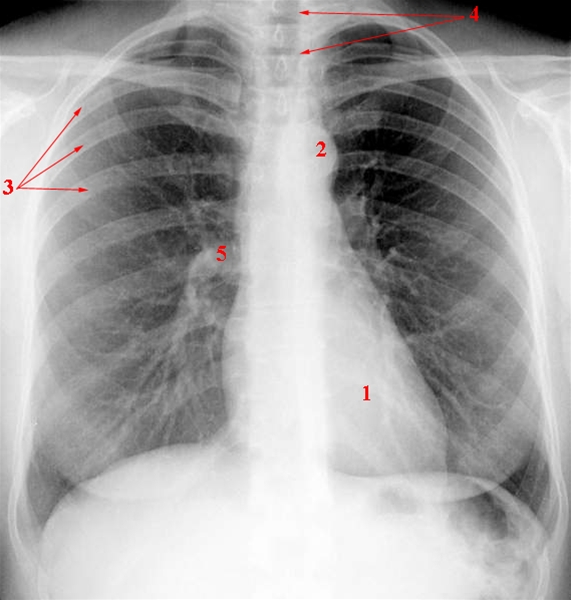

Thorax, røntgen, normal

Tegningen viser:

1. Hjerteskygge

2. Aortaknoppen

3. Costae (ribben)

4. Trakea (luftrør)

5. Lungehilus